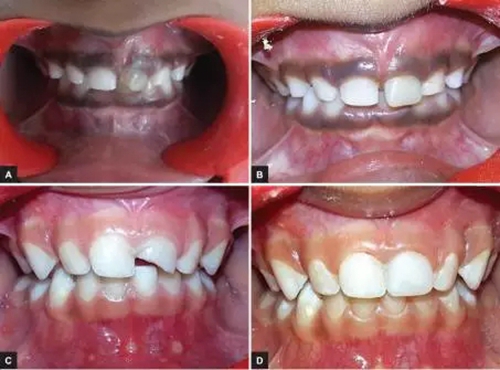

本研究中,其他患齲齒或牙外傷的患兒均采用此方法使用臨時(shí)冠材料進(jìn)行美學(xué)修復(fù),下圖分別為兩例乳前牙齲齒(圖2)和兩例牙外傷(圖3)的病例。

圖2.(2-A,2-B為乳前牙齲齒病例1 2-C,2-D為乳前牙齲齒病例2)

圖3.(3-A,3-B為乳前牙外傷病例1 3-C,3-D為乳前牙外傷病例2)